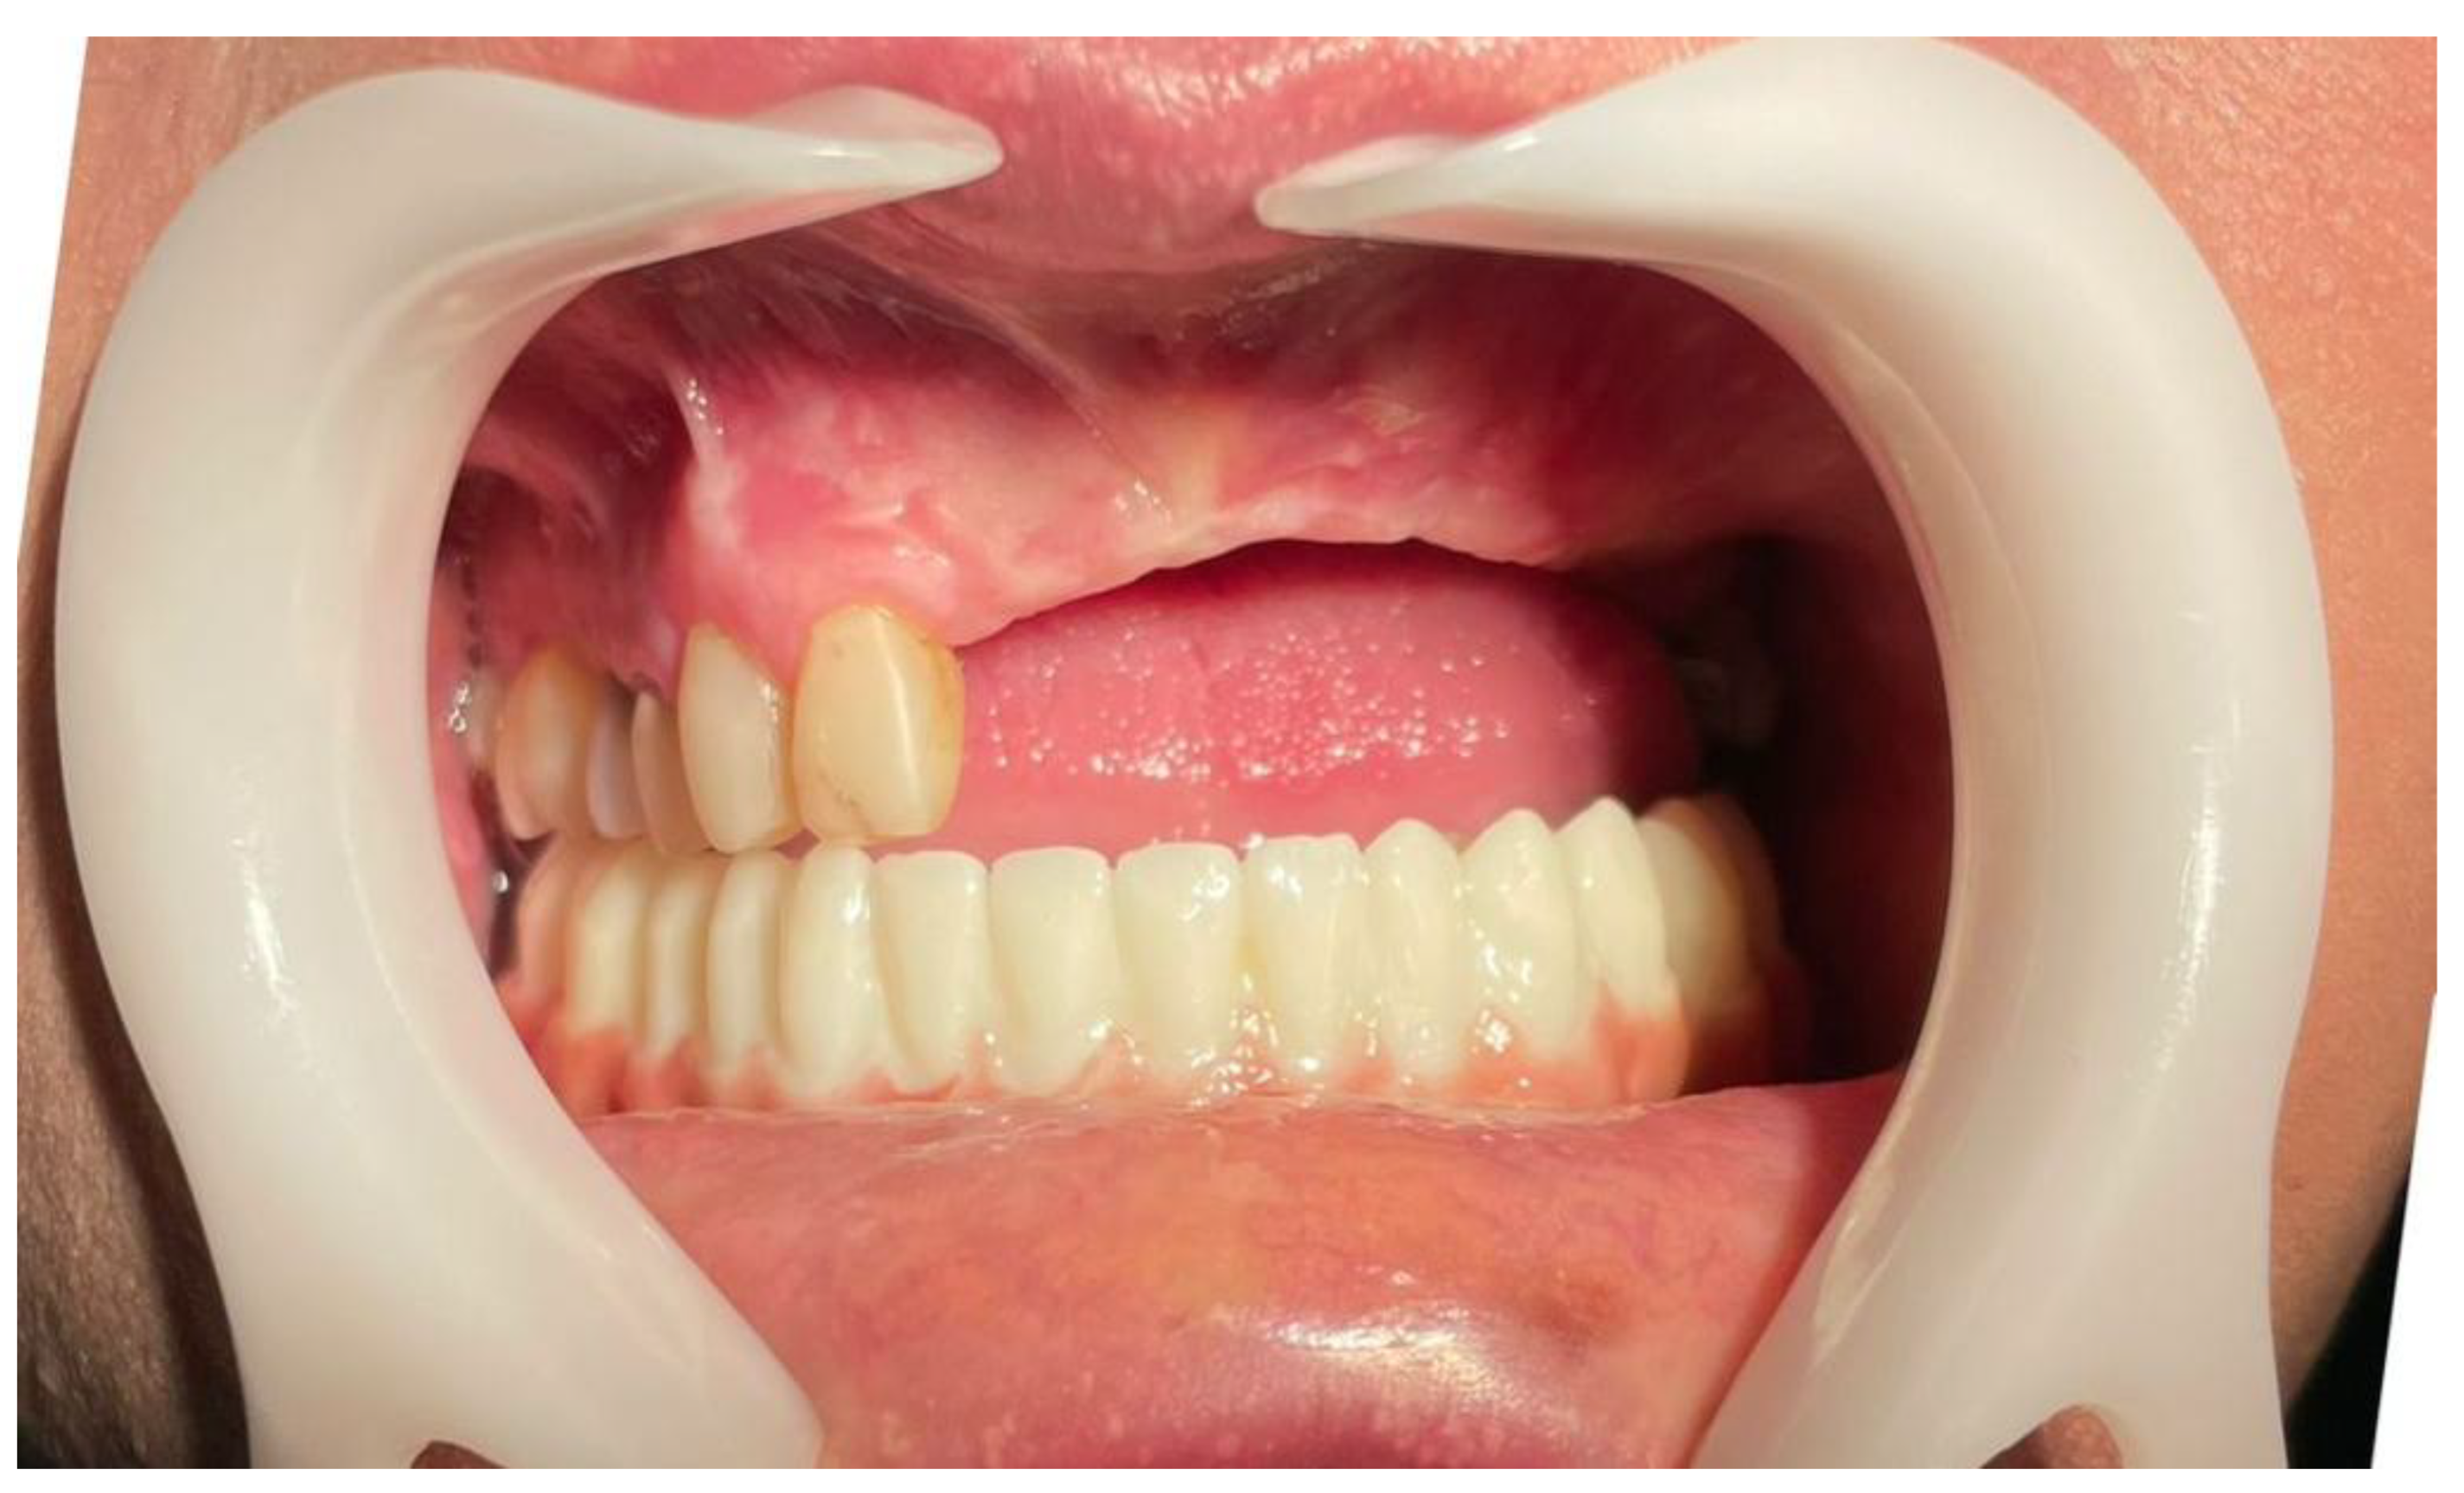

Healing abutments were connected six months following implant placement Figure 10. The patient reported no pain, swelling, or complications during the 12-month follow-up period

A final panoramic radiograph was obtained following healing abutment placement to verify implant positioning and peri-implant bone stability (Figure 11). Two weeks later, a follow-up clinical photograph demonstrated healthy soft tissue contours before referring the patient for the prosthetic phase (Figure 12).

Figure 12. Clinical view taken two weeks after healing abutment placement, showing healthy soft tissue contours prior to referral for prosthetic rehabilitation.